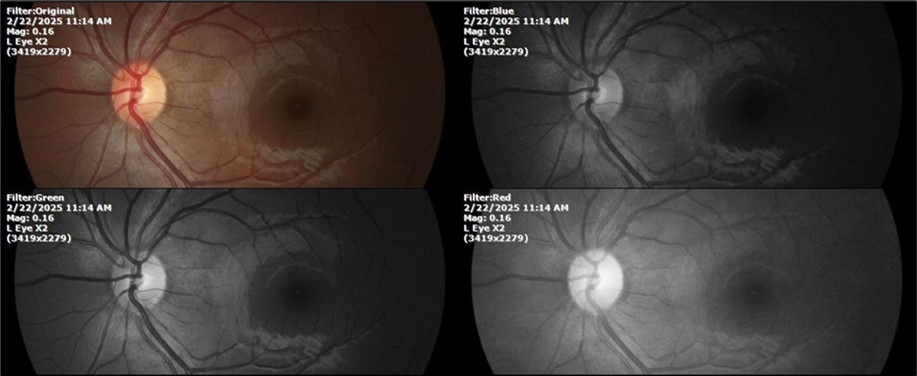

February 22, 2025

There is no pain, only minimal discomfort, and my vision has improved (Figure 20, Figure 21, Figure 22, Figure 23, Figure 24)

Figure 22.The whitish mass of phantom cells continues to decrease. The treatment continues to be based on ǪIAPI 1®, sublingual drops, three drops every hour, for as long as the patient is awake.

Figure 23.The mirror reflection of the left eye, without anomalies.

Figure 24.The eye that was not affected by the trauma (left side) remains in good condition.